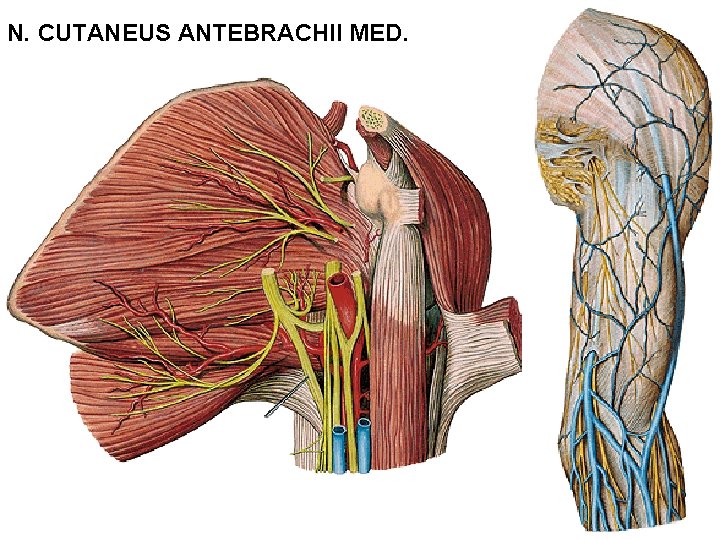

N. CUTANEUS ANTEBRACHII MED.

N. CUTANEUS ANTEBRACHII MED. - r. anterior - r. posterior (ulnaris)